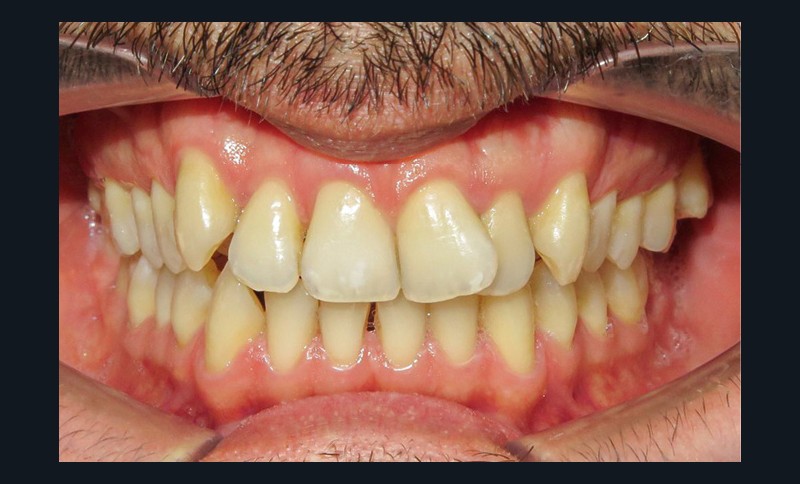

Diagnostic (fig. 1a-i)

Le patient consulte initialement pour des défauts d’alignement. L’examen clinique confirme l’existence d’un encombrement antérieur bimaxillaire, mais révèle aussi la présence d’une Classe II dentaire sévère, d’une exoclusion de la 27 et de troubles parodontaux (peu ou absence de papilles inter-dentaires). Sur le plan squelettique, le patient est relativement équilibré avec un profil harmonieux.